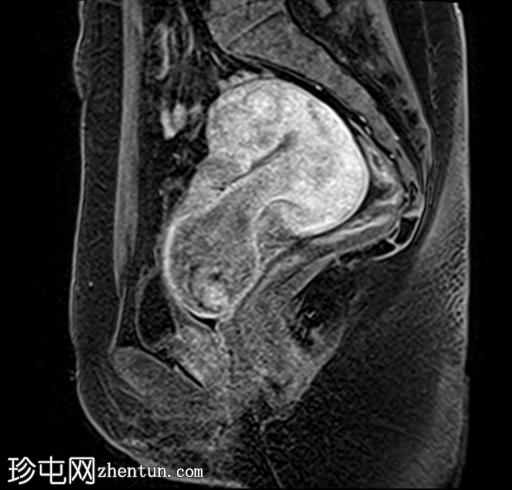

矢状位

T2加权像

子宫增大,前倾后屈,可见多发大小不一、位置各异的壁内肌瘤(主要位于Figo 2、5和6区)。

一个边界清晰的带蒂宫腔内肿块经扩张的宫颈管脱出。T1加权像上呈等信号,T2加权像上呈中低信号,周围环绕着高信号的子宫内膜,静脉注射对比剂后呈明显不均匀强化。

双侧卵巢外观正常,可见小卵泡。

MRI 影像特征最符合带蒂子宫肌瘤经扩张的宫颈管脱垂,并伴有多个子宫肌瘤。